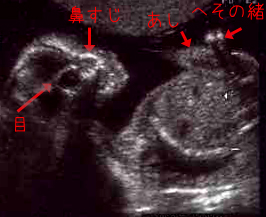

現在、20W5D(20週と5日)。

<※クリックで拡大>

全体が画面に収まらないからか、今回は身長を測ってくれませんでした。

頭の幅は5.10cm(21W相当)。

前回の写真を見てみると4.19cmとなっているので

ひと回り大きくなったというところです。

心臓の部屋がはっきり4つに分かれているのまで見えたんですけどねえ。